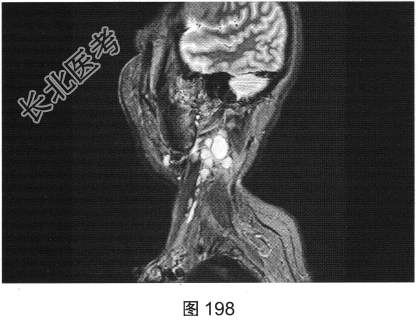

- 简答题2、患者行颈部平扫MRI检查,如图196~图199所示。请问患者MRI检查的阳性影像学表现有哪些?